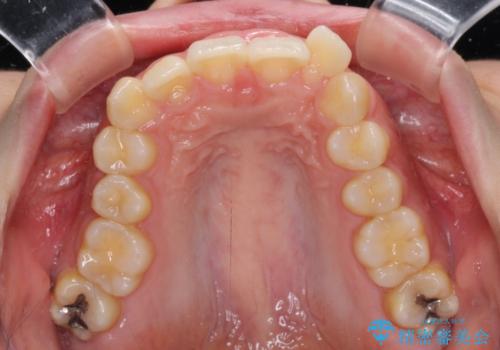

下顎前歯が隠れて突出した口元 ワイヤー装置での抜歯矯正

- 前歯のデコボコと口元の突出感を気にして来院された患者様です。

下顎骨の左右差や、上顎骨の前方位などが認められたため、上下左右の第1小臼歯4本を抜歯し、ワイヤー装置にて矯正治療を行うこととしました。

骨格的な左右差がありましたが、何とか当初予定していた期間で、左右対称の咬み合わせに仕上げることができました。